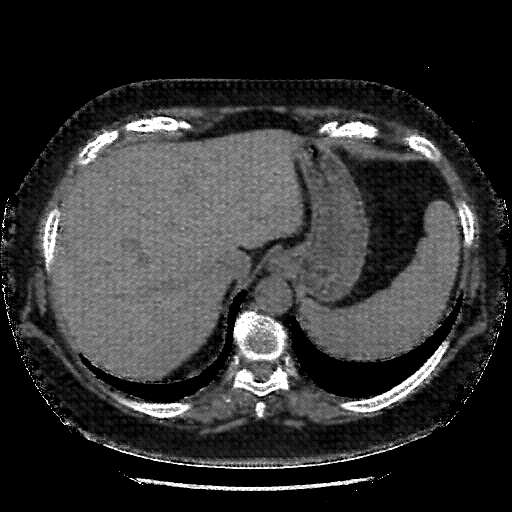

Image Grid

4Γ—3 grid: Rows show different image types (Original NATIVE, Reconstructed NATIVE, Original VENOUS, Generated VENOUS), Columns show windowing techniques (No Window, Lung Window, Mediastinum Window)

Generated VENOUS CT scan (A→B translation)

No window - Raw intensity values